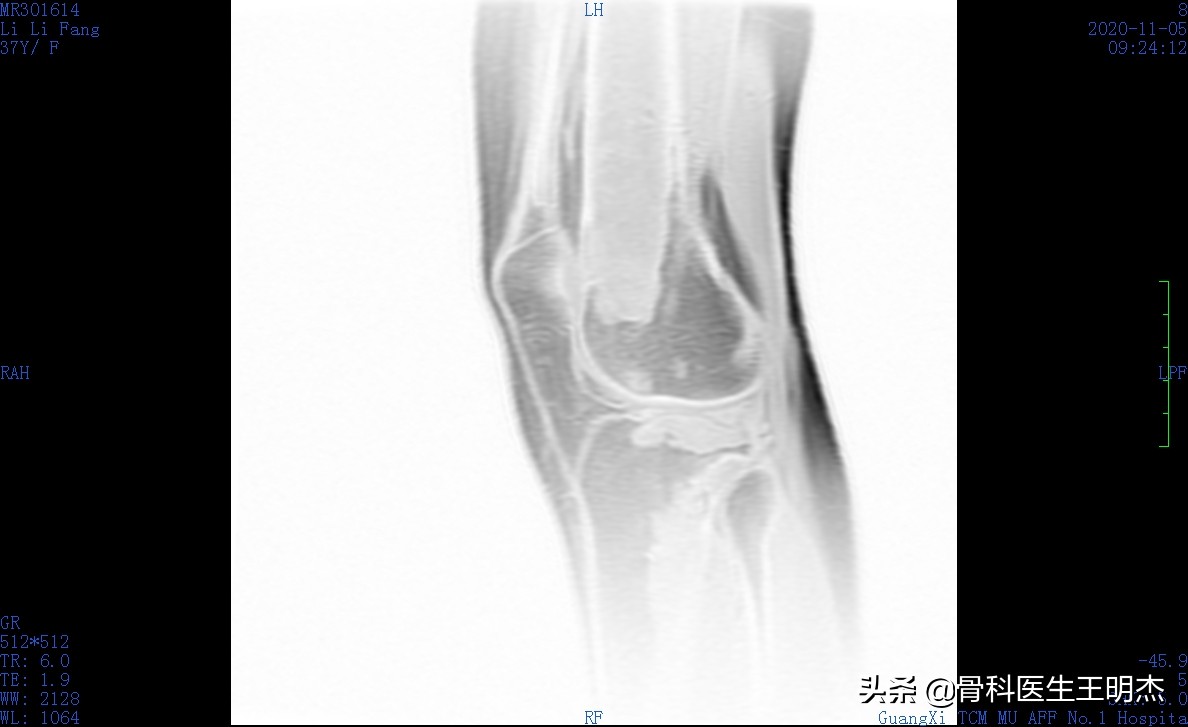

骨梗死又称骨髓梗死、骨脂肪梗死, 指发生于干骺端和骨干的骨性坏死, 多发生于股骨下端、胫骨上端和肱骨上端, 呈多发性和对称性改变。

临床上, 骨梗死可分为两种类型: (1) 单纯骨干及干骺端型骨梗死; (2) 骨干骨梗死合并关节面骨坏死 (以膝关节常见) 。

骨梗死发生后则进入骨修复阶段, 包括血管再生、肉芽组织生成、死骨吸收、新生骨形成。血管再生是骨修复的开始, 死骨吸收, 形成纤维结缔组织和致密新生骨则是骨梗死的晚期阶段。骨梗死在演变的过程中有3个基本病理改变, 即死骨块、吸收带 (充血、水肿带) 、新生骨带, 是骨梗死X线、CT、MRI等影像学诊断的基础。